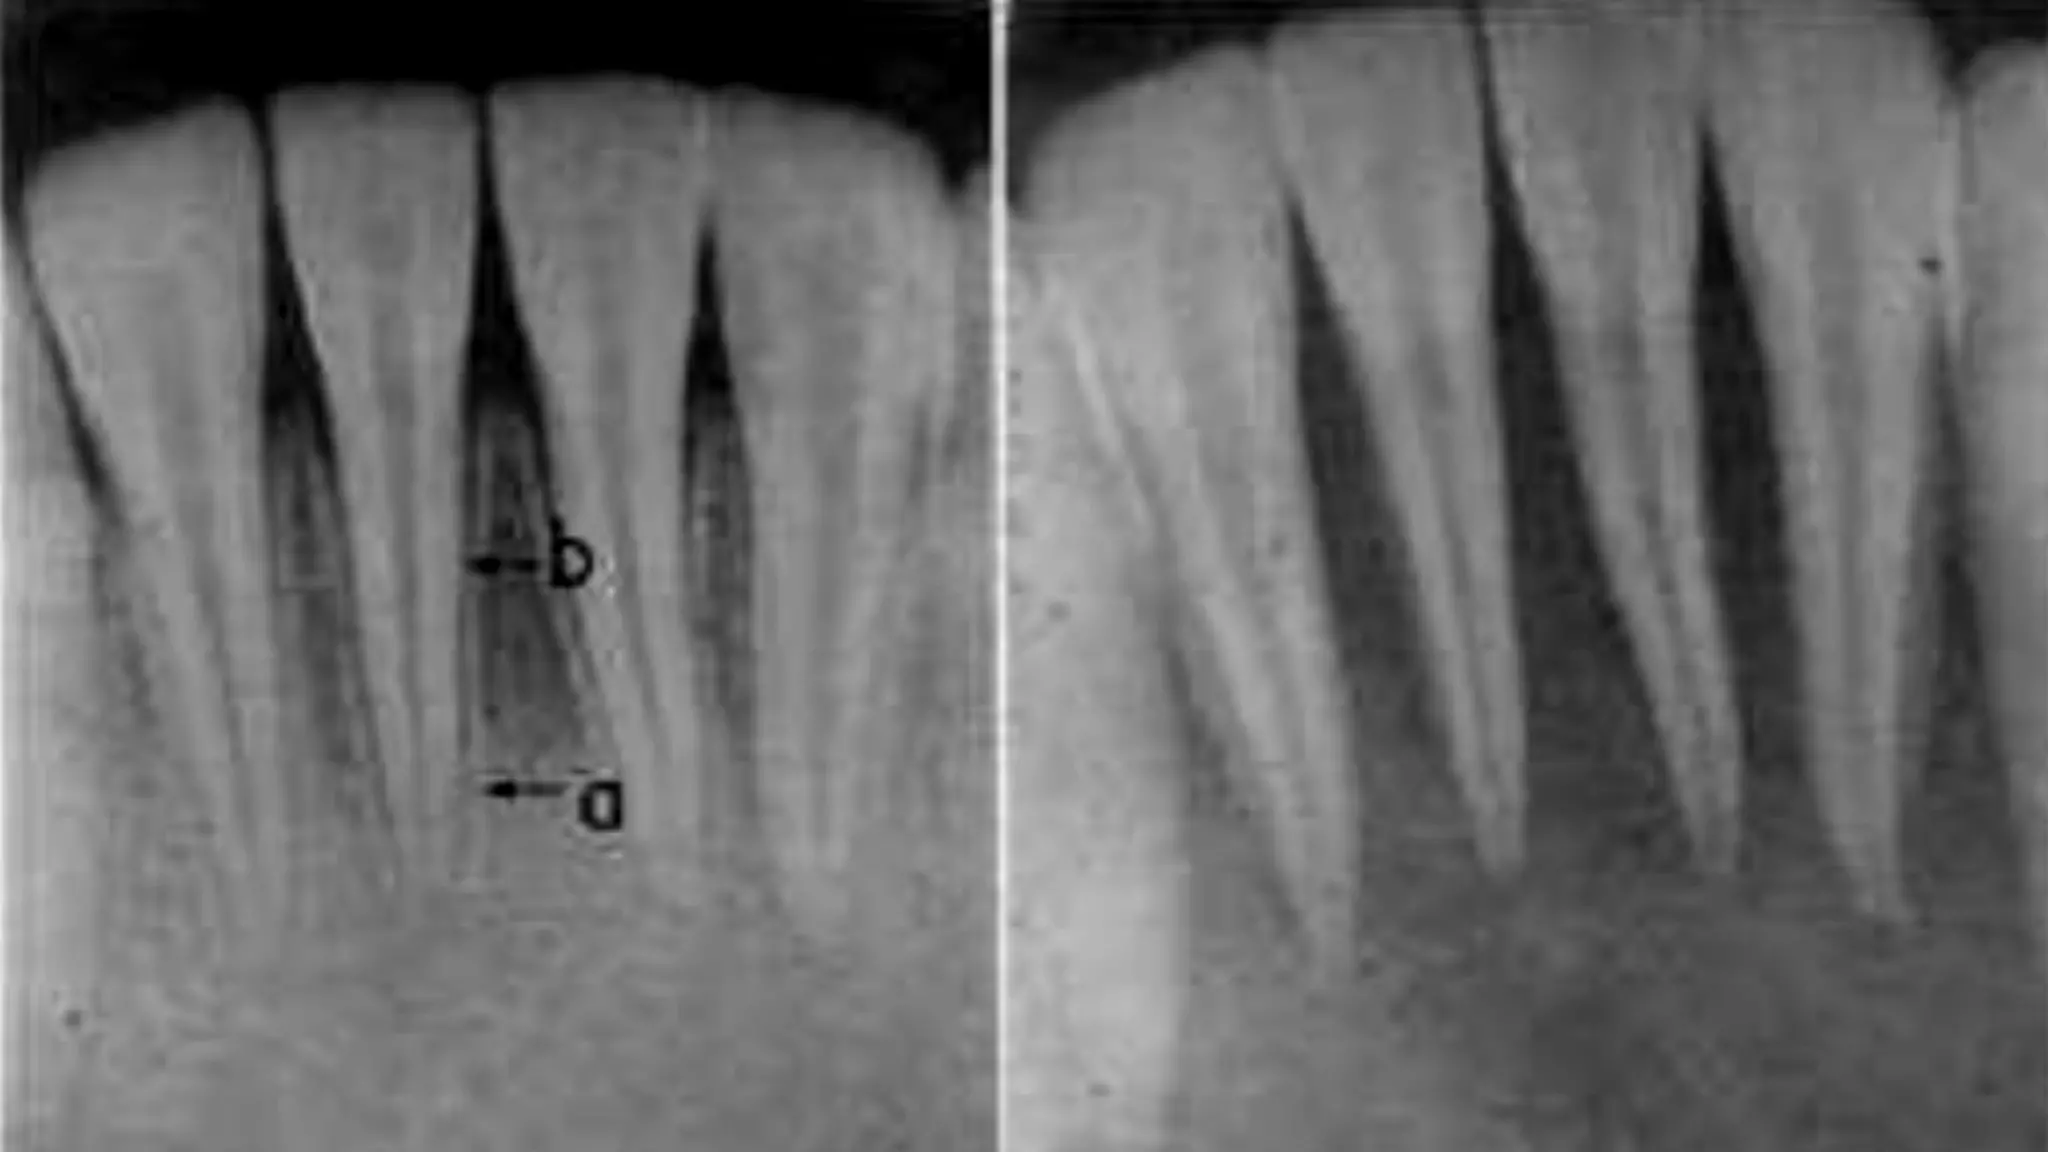

The mean distance between the major and minor diameters

0.5 mm in a young person and 0.67 mm in an older individual.

The increased length in older individuals is due to the increased

buildup of cementum

According to Kuttler, the narrowest diameter of

the canal is definitely not at the site of exiting of the

canal from the tooth but usually occurs within the dentin,

just prior to the initial layers of cementum.

He referred to this position as the minor diameter

of the canal, although others call it the apical constriction.

The diameter of the canal at the site of exiting from the

tooth (major diameter) was found to be approximately

twice as wide as minor diameter. This means that the

longitudinal view of the canal as a tapering funnel to the

tip of the root is incorrect.